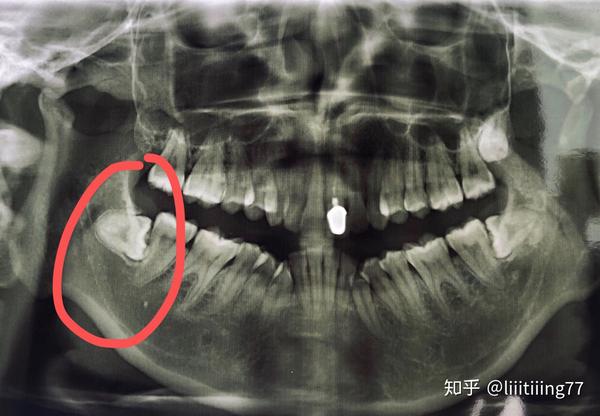

医生给看了片子,说了句打脸了吧!还是三颗呢!顿时就懵了…我在这个拔牙的问题上非常害怕,人生第一次拔牙,妥妥的怕!瞬间,我慌的一批,没有立即拔牙,怂的开车回家了,甚至不知道怎么把车开回家的!

这个过程持续的时间非常久,医生跟我说完要出来了,结果又拔了20分钟……我的牙齿坚硬且非常脆,动不动就碎掉了,而且真的很大,医生都怀疑我这么小的人怎么会有这么粗大的牙!